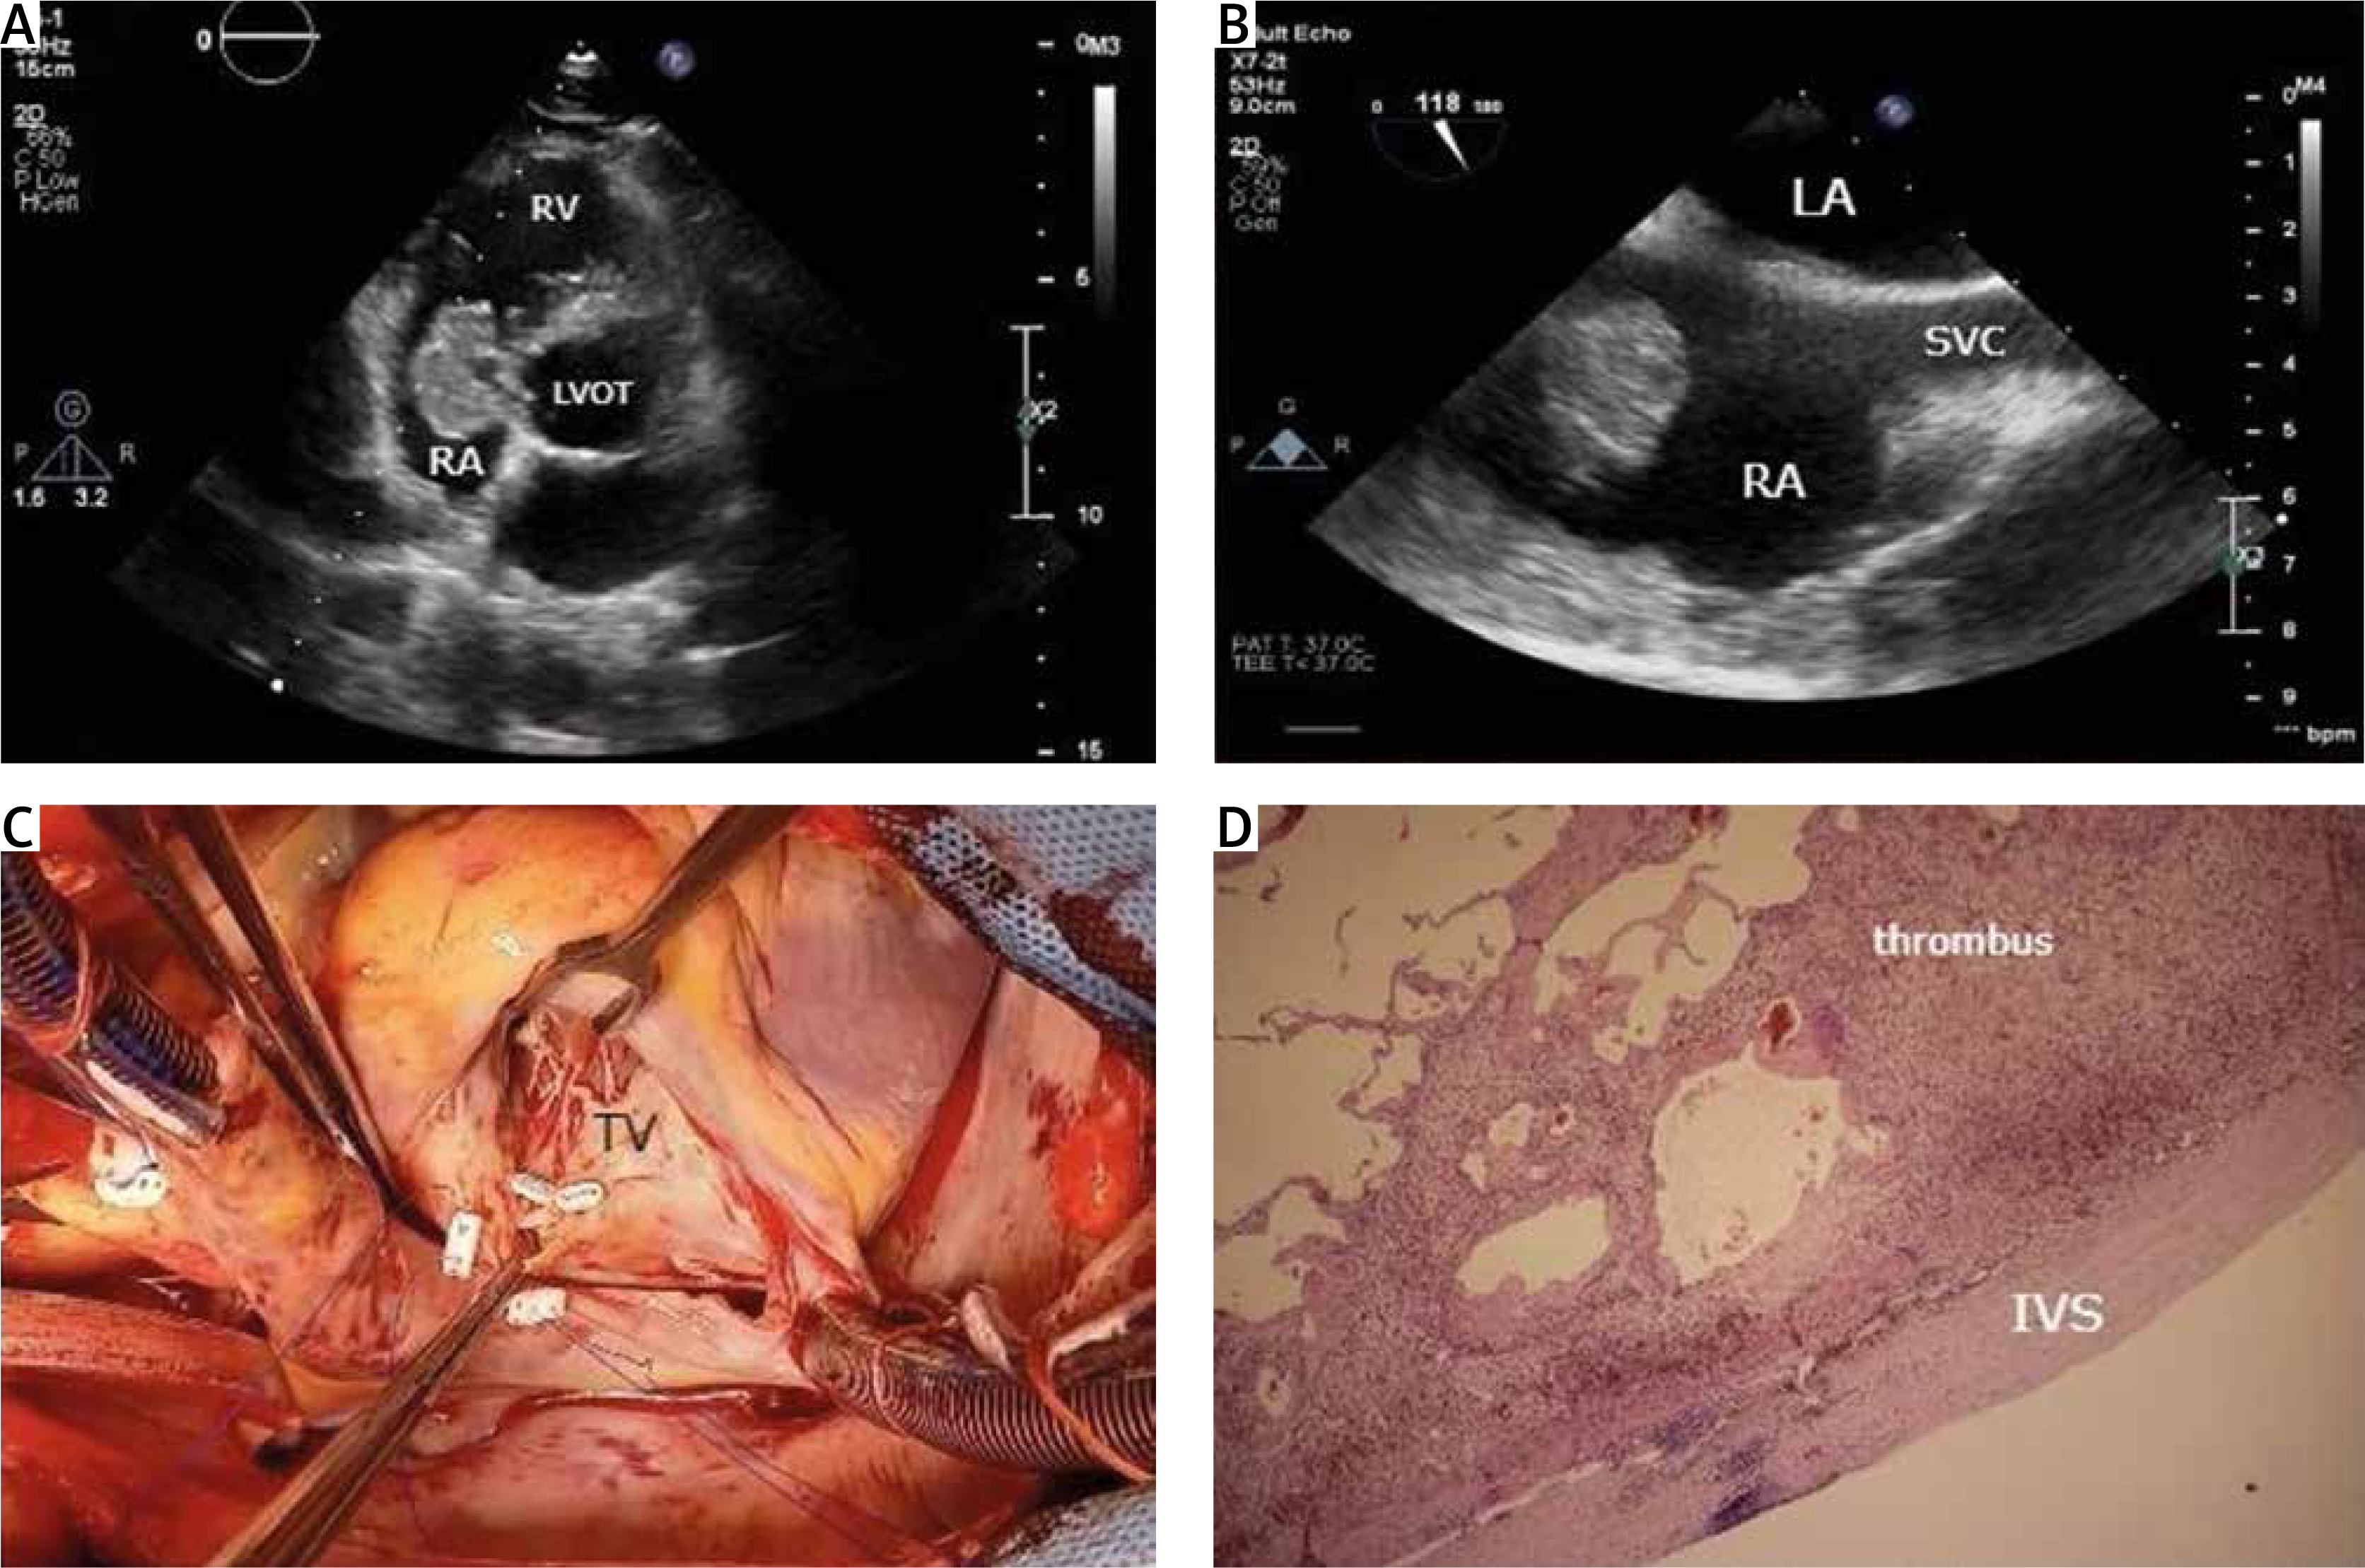

Aneurysm of the atrioventricular septum mimicking a right atrial mass with thrombus is uncommon and a handful of reports have been described [1, 2]. We present a rare case of an incidental finding in transthoracic echocardiography (TTE) of a right atrial tumor mimicking myxoma above the septal leaflet of the tricuspid valve in the membranous septum, in a 65-year-old male asymptomatic patient. No left-to-right shunt was observed (Figures 1 A, B). The TTE was performed as part of preventive examinations. Intraoperatively, a left ventricular-right atrial communication (Gerbode-type defect), accompanied by an aneurysm of the atrioventricular septum filled with thrombus, was found in the right atrium (Figure 1 C). Histology confirmed the finding (Figure 1 D). He underwent successful extirpation of the tumor and closure of the communication between the right atrium and the left ventricle. Moreover, other right atrial masses that can present as myxoma on imaging include benign and malignant primary cardiac tumors, metastatic cardiac tumors, a prominent eustachian valve, sessile or mobile thrombi, vegetations of the tricuspid valve, and different intracardiac objects (pacemaker leads, central venous catheters, needles, and even bullets) [3].

Figure 1

A, B – Echocardiographic images showing the right atrial atrioventricular septal aneurysm; C – intraoperative image; D – histological image showing the thrombus and the interventricular septum

RV – right ventricle, RA – right atrium, LVOT – left ventricular outflow tract, LA – left atrium, SVC – vena cava superior, TV – tricuspid valve, IVS – interventricular septum.